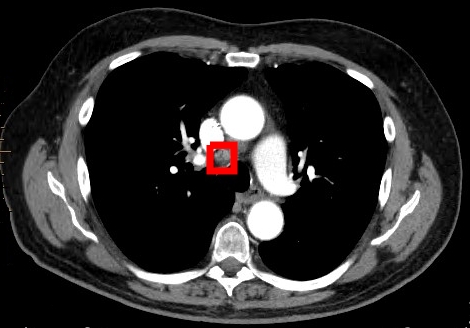

Fig. 2: Visual results produced by our proposed method on the RAH data set. Image 2(a) shows the positive classification of an scan containing a metastatic lymph node (marked in red). Image 2(b) contains the negative classification of an image with non-metastatic lymph nodes.